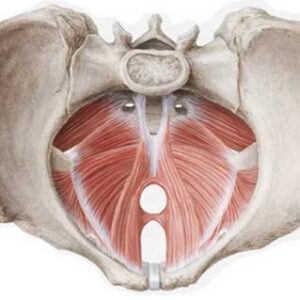

Il pavimento pelvico (diaframma pelvico)

Pavimento Pelvico (diaframma pelvico) Il diaframma pelvico è contenuto tra le ossa del sacro e del bacino (ileo, ischio, pube). È composto da strati muscolari che vanno a formare il pavimento della cavità addomino-pelvica. I muscoli che lo compongono sono l’ileo-coccigeo, l’ischio-coccigeo, il pubo-coccigeo, il coccigeo, il pubo-rettale e i muscoli anali. Il diaframma pelvico...